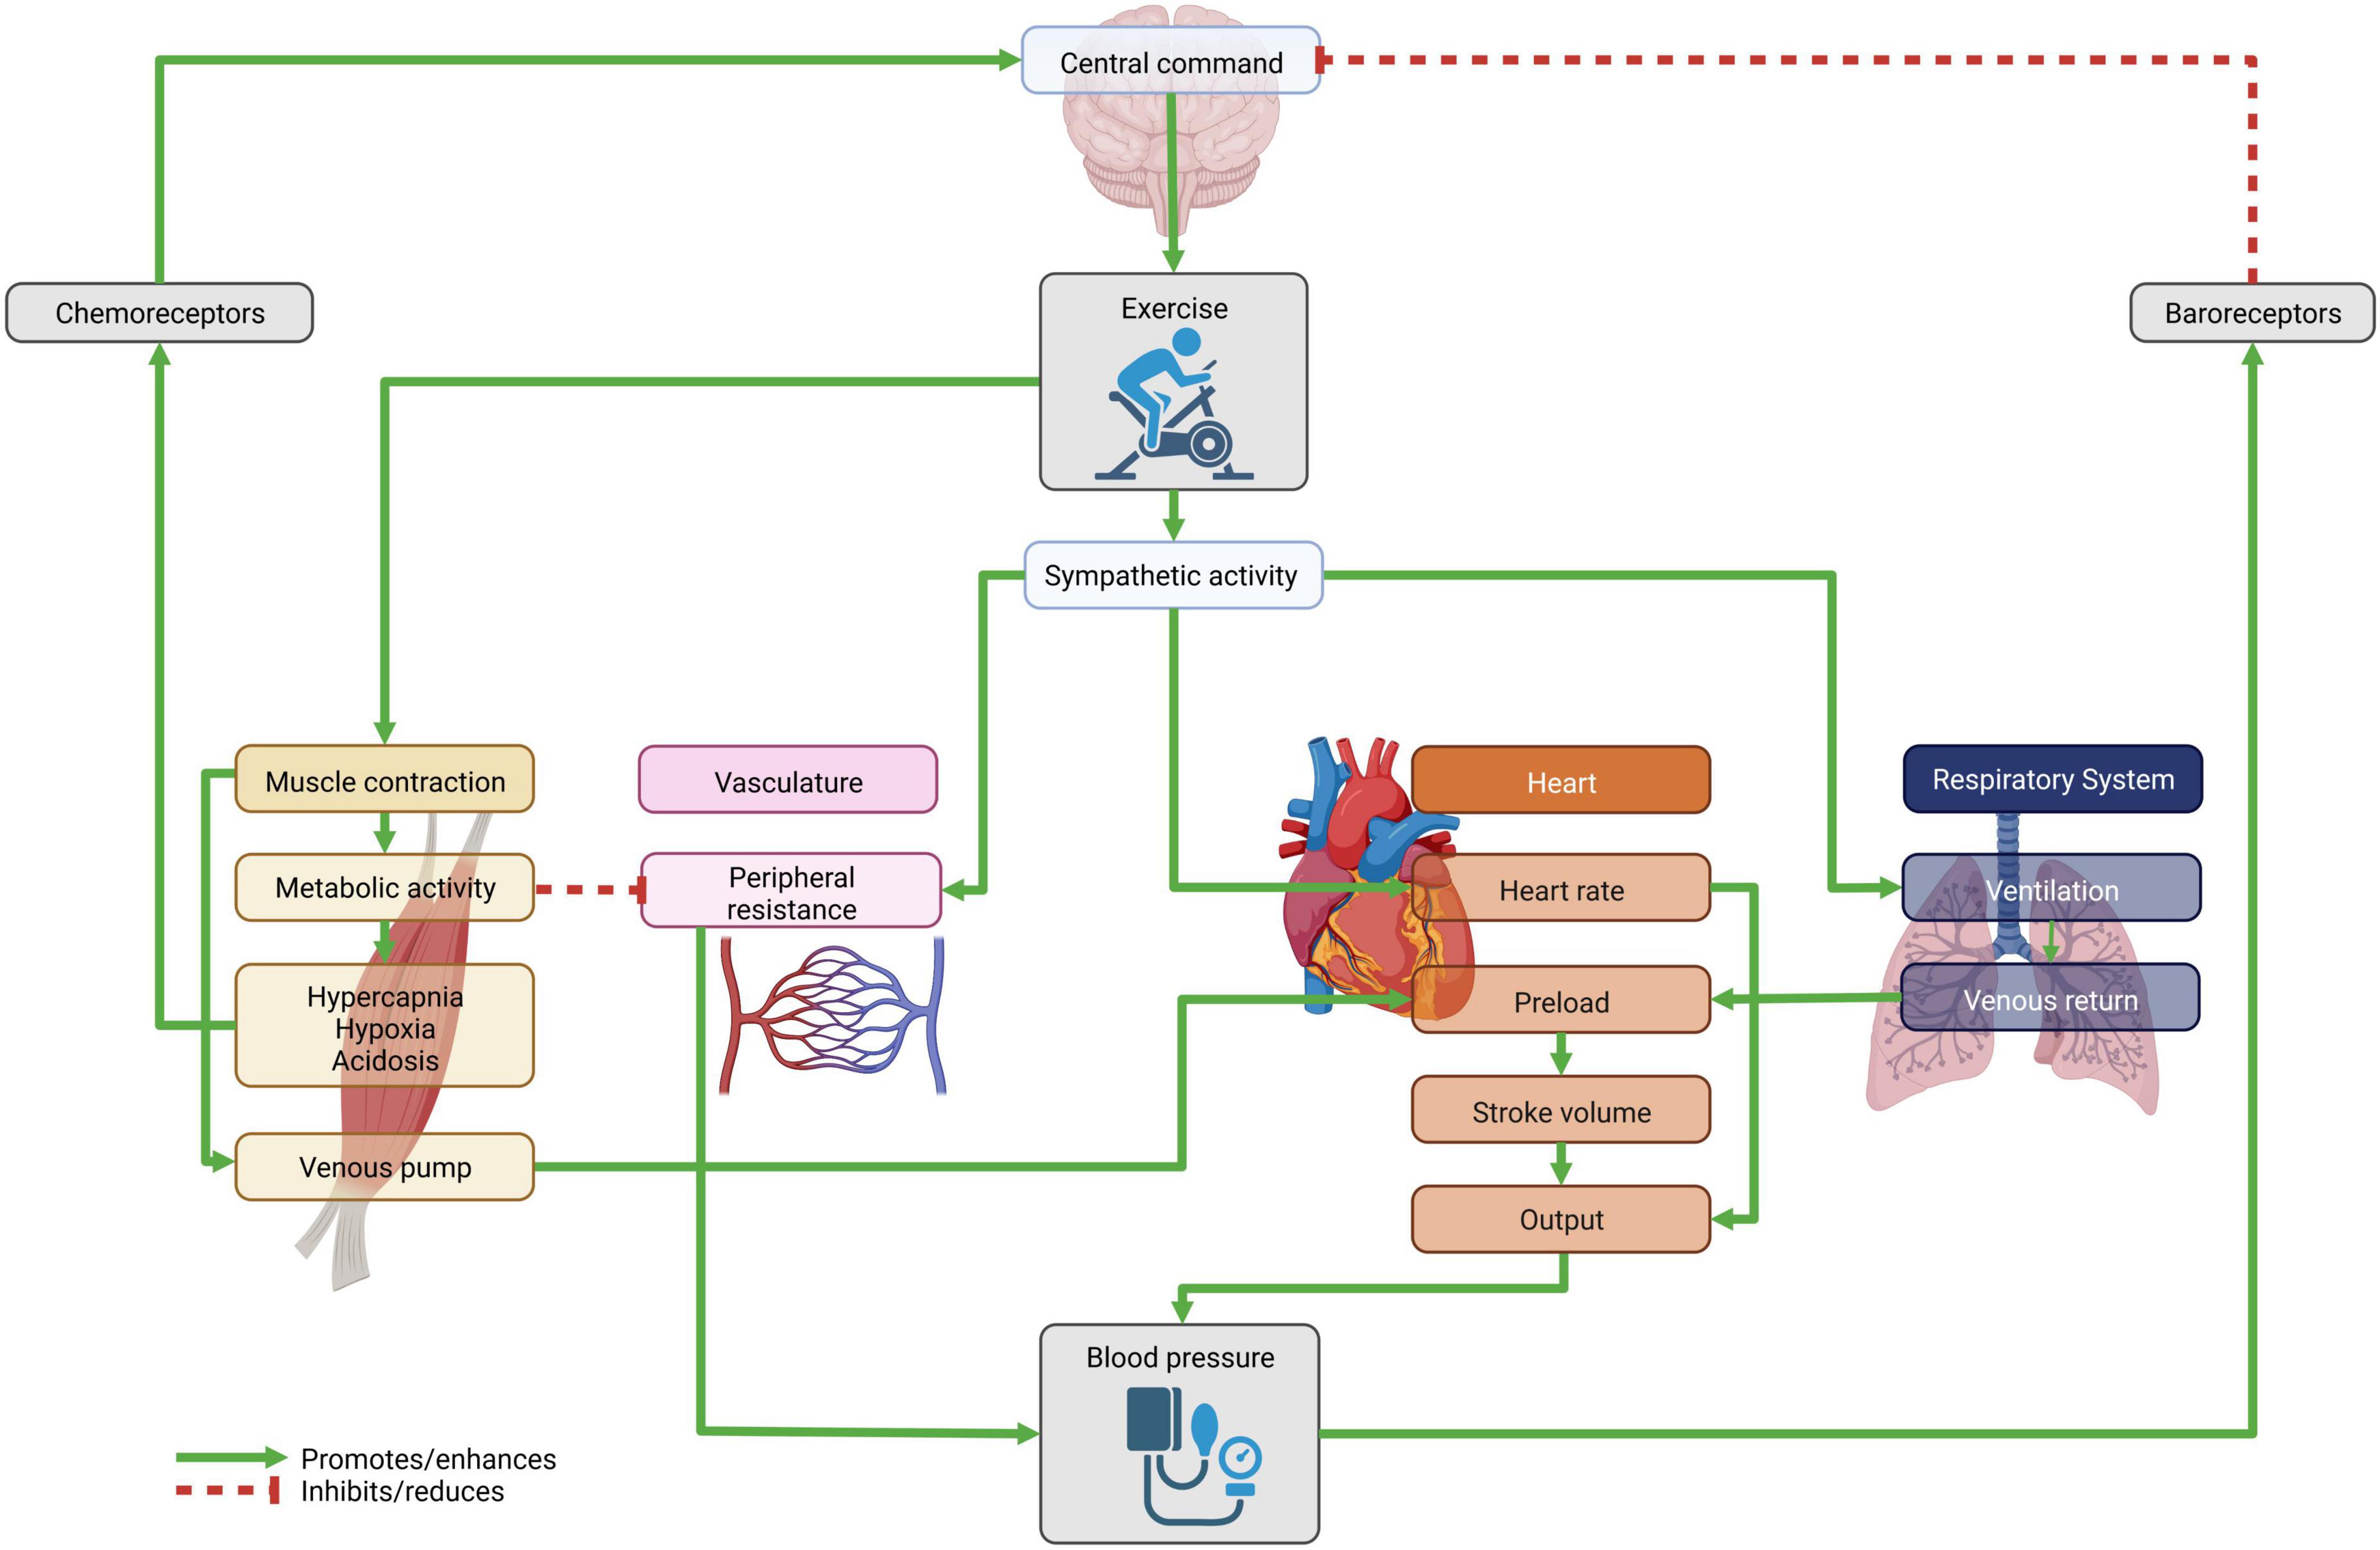

Frontiers Blood Pressure Response To Exercise In Children And Adolescents

Frontiers Blood Pressure Response To Exercise In Children And Adolescents

Diagram Blood Pressure During Exercise